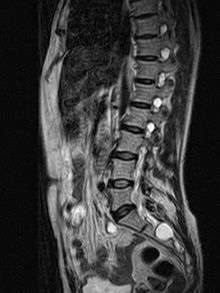

MRI sagittal image of sacral and dorso-lumbar perineural cysts.

MRI, or Magnetic Resonance Imaging, is considered the imaging study of choice in identifying Tarlov cysts. MRI provides better resolution of tissue density, absence of bone interference, multiplanar capabilities, and is noninvasive. Plain films may show bony erosion of the spinal canal or of the sacral foramina On MRI pictures, the signal is the same as the CSF one.